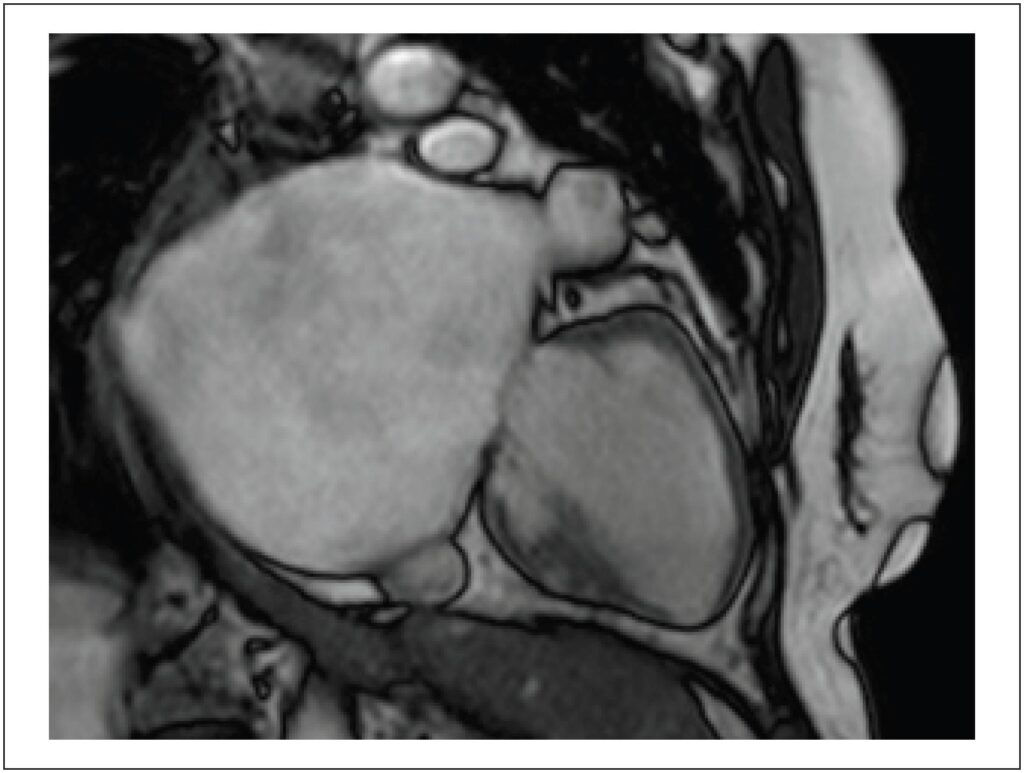

Giant Left Atrium in Rheumatic Mitral Valve Disease

The Giant Left Atrium (GLA) is a rare condition, more commonly related to rheumatic mitral valve disease; it can be mistaken with a few possible differential diagnoses when less accurate methods are implemented, potentially leading to particularly dangerous and unnecessary procedures in this setting. Cardiovascular imaging methods, such as Cardiac Magnetic Resonance (CMR), can be valuable for this differentiation and provide high spatial resolution, supporting accurate diagnosis and surgical planning when indicated. Selecting the most precise diagnostic method, however, requires deep knowledge of the GLA condition and clinical data, leading to a correct suspicion. Furthermore, opting for using volumetry rather than the biplanar method in cases of significant deformity ensures greater accuracy in the values obtained.